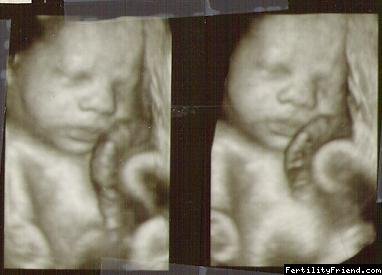

Obrázky z 3D ultrazvuku - 26. týden těhotenství